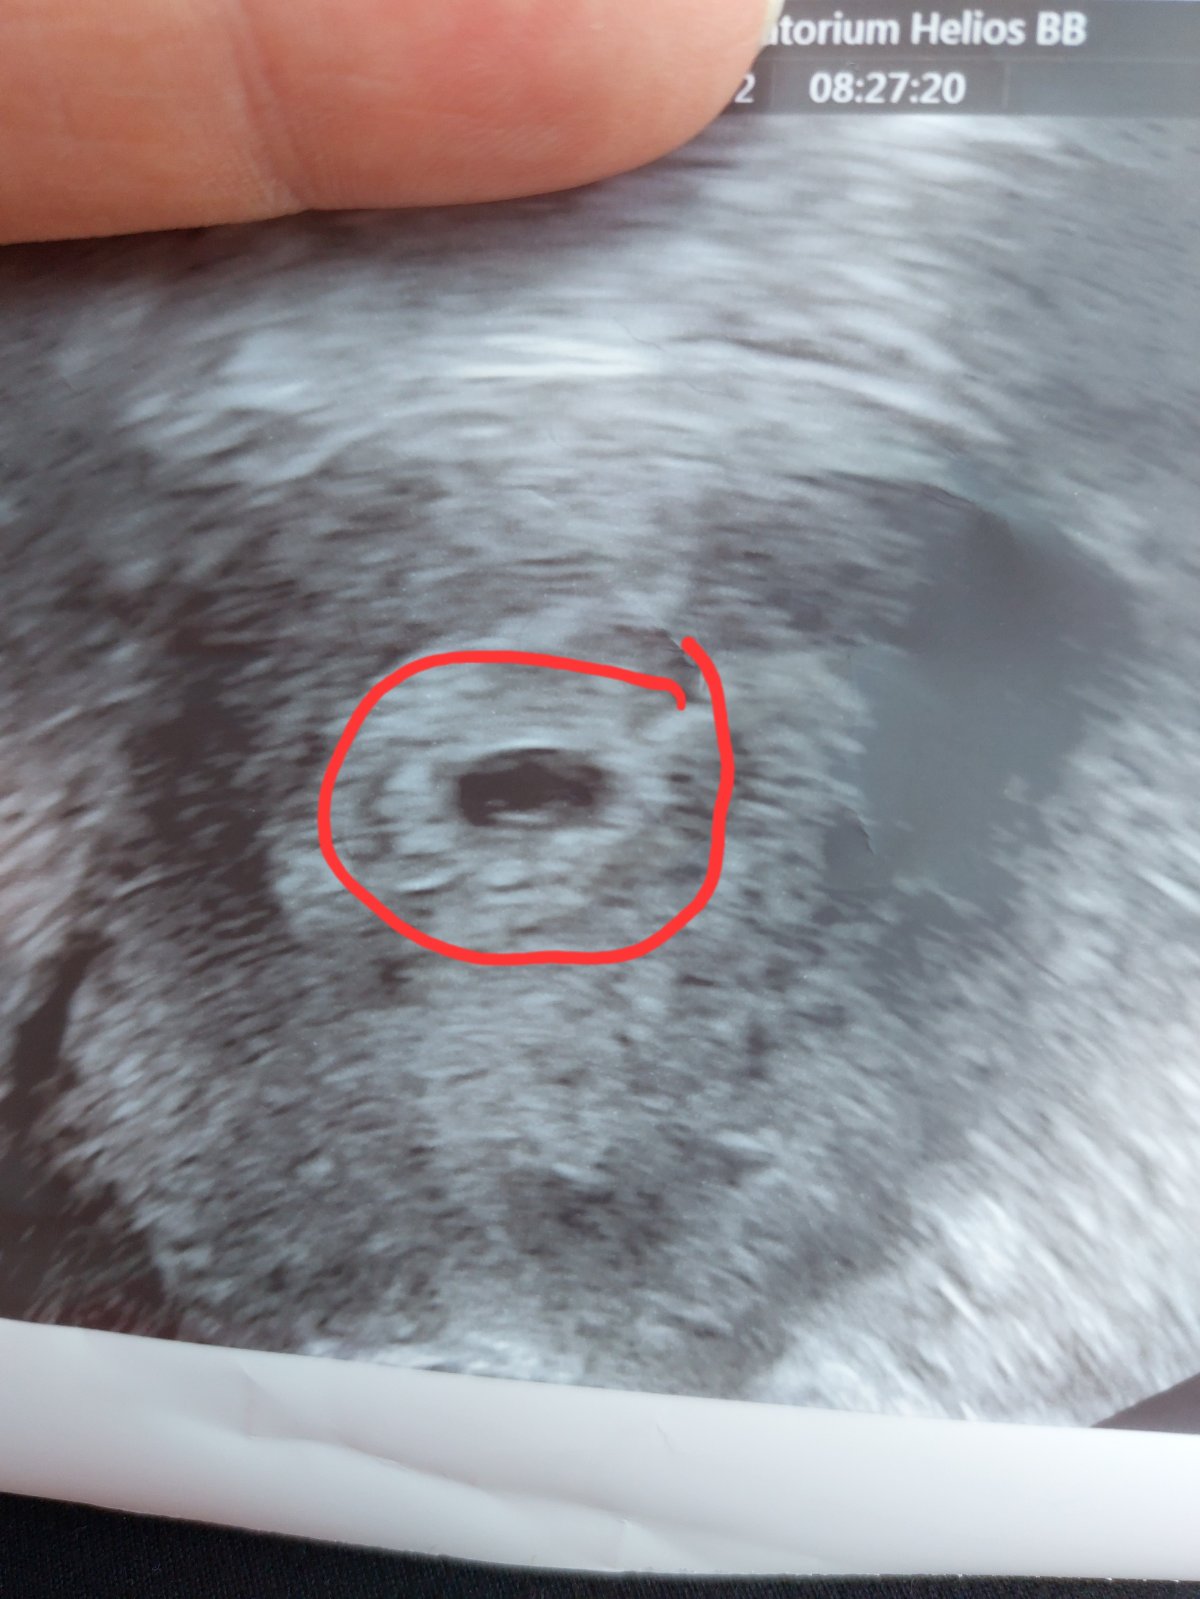

@jarrys na kontrole vsetko v poriadku,vacok ma 8 alebo 9mm nepamatam presne. Hemarom nevideli ziadny cize preco spinim nevedia ale vnutri ze mam vsetko pekne ciste a krasne tak ako ma byt. Na sone bolo vidno uz aj mini ciarocku babatinka. Lieky mam brat stale tak ako beriem. Kontrola opat o tyzden. Ak by cokolvek bolo tak samozrejme ze nech hned volam. A ze nech sa nestresujem. Vravim reku ale pri malom som toto nemala tak je to pre mna stres. Rano mi bolo spatne tak ako vcera,aj sa mi hlava tocila,aj divno od zaludka. Ledva som zjedla pol keksiku a lieky vypila a chvilu mi bolo moc teplo,chvilu chladno. Ruky chvilami take tazke. No reku az to pojde takto dalej tak o tyzden bude musiet ist chlap so mnou a soferovat on. Uz je lepsie a aj sme bezpecne prisli domov.